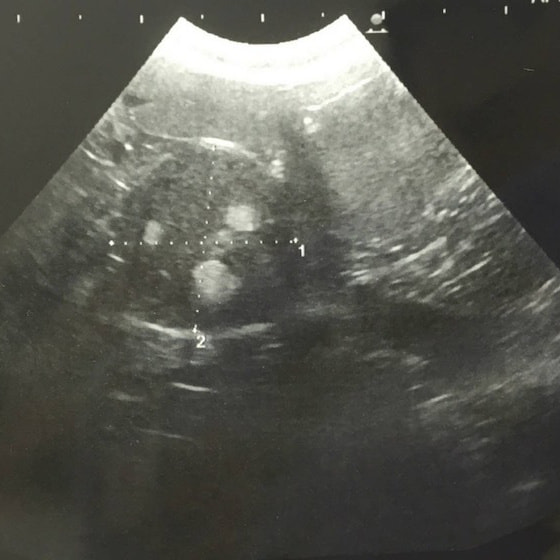

エコー検査